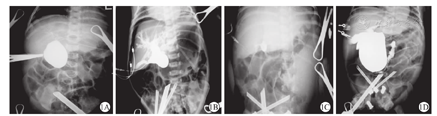

碘海醇通过胆囊或囊肿注入后,所有囊肿均有显示。24例Ⅰ型CBA患儿均有肝内胆管显影(图1A),其中包括6例患儿肝内胆管扩张(图1B)。5例Ⅲ型CBA患儿囊肿与肝内外胆管无相通(图1C)。所有CBA患儿十二指肠均无显影。67例CC患儿肝内胆管均有显影,其中包括29例患儿肝内胆管扩张,大部分CC患儿囊肿与十二指肠相通(图1D)。CBA组包括24例Ⅰ型和6例Ⅲ型囊肿型胆道闭锁患儿,24例Ⅰ型CBA患儿行肝管空肠吻合术,5例Ⅲ型CBA患儿行肝门空肠吻合术。CC组患儿均行肝管空肠吻合术。

胆道造影是目前区分CBA与CC的可靠方法。本研究中,术中胆道造影示,Ⅰ型CBA肝内胆道可显影,有一部分肝内胆管显影呈云雾状(图1A),一部分肝内胆管扩张(图1B)。Ⅰ型CBA患儿的囊肿与肝内外胆管相通,但与十二指肠不相通。Ⅲ型CBA患儿的囊肿与肝内外胆管不相通,且十二指肠无显影(图1C)。CC患儿的囊肿与肝内胆管及十二指肠均相通(图1D)。肝内胆管显影不佳预示可能与胆汁分泌量少有关,囊肿大小可以反映肝内胆汁流量与胆汁流入十二指肠的梗阻程度。